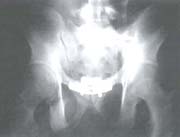

De acuerdo a la clasificación AO para trauma pélvico, todos los pacientes se diagnosticaron como Tipo C. El tipo de lesión traumática más frecuente fue luxofractura de la articulación sacroiliaca, 10 pacientes (46%); de éstos, 6 pacientes (25%) derechos y 4 pacientes (21%) izquierdos (figuras 4A – 4B – 4C – 4D).

Fig. 4D Radiografía postoperatorio donde se aprecia la fijación con tornillos iliosacros y placas en la sín